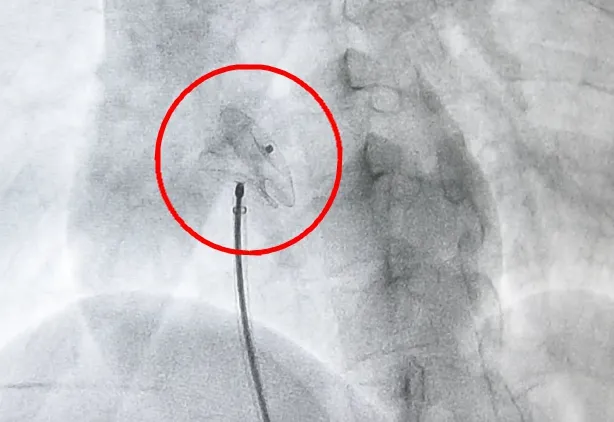

2.脑动脉瘤栓塞术:

开展前交通动脉瘤、后交通动脉瘤、脉络膜前动脉瘤、大脑中动脉瘤、基底动脉瘤栓塞术。